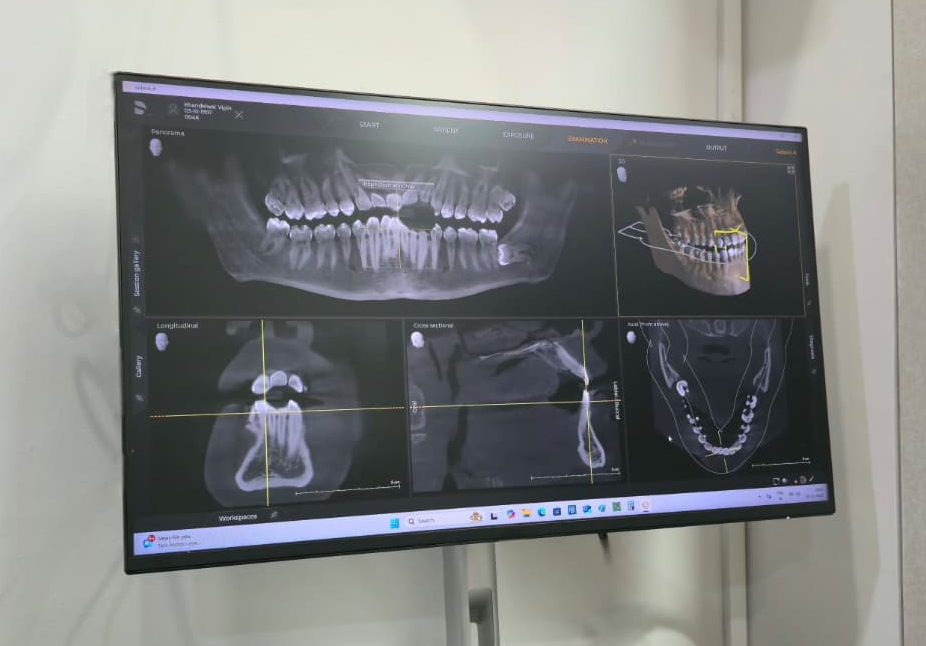

CBCT & OPG Scans – Precise Diagnosis

With 3D imaging, we can accurately assess the teeth, gums, and jawbone. Our experts can spot problems early and devise the most accurate treatment plan with a CBCT dental scan.

With 3D imaging, we can accurately assess the teeth, gums, and jawbone. Our experts can spot problems early and devise the most accurate treatment plan with a CBCT dental scan.

The use of digital impressions and the intuitive user interface make the design of individualized restorations simple, fast, and easy. Along with CBCT dental scan and OPG dental imaging, every treatment is precisely planned for a better impact.

Our process starts with a comprehensive evaluation. Precise 3D imaging of the mouth captures every detail of your teeth, gums, and jawbone closer to reality than ever before—allowing us to diagnose immediate dental treatment with a higher level of accuracy and effectiveness.